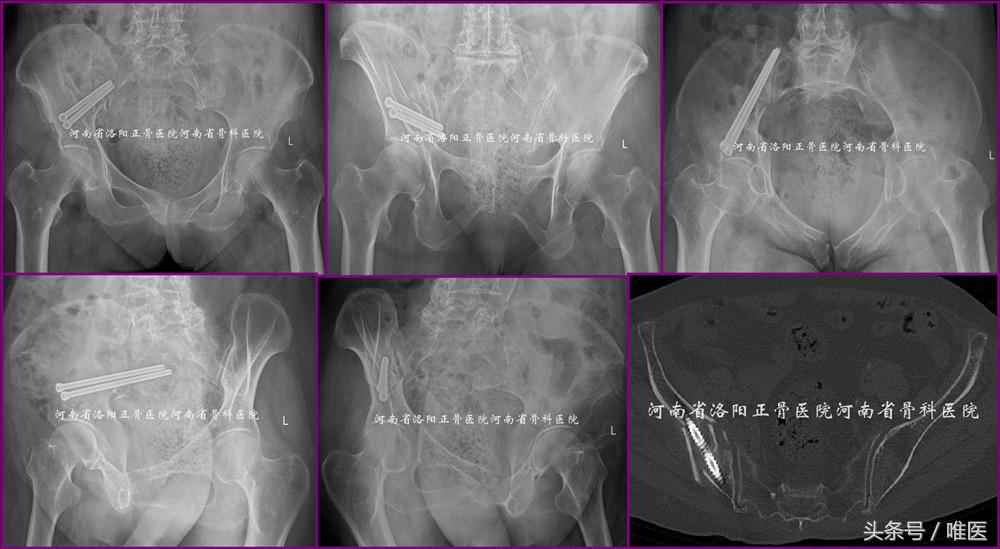

病例1:即本文第一部分所述病例。术前影像资料见图1。术后影像资料见图11。病人术后第一天即坐起活动而有效地降低了卧床并发症。此处给出开篇问题的答案。

图11. LC-II螺钉的经皮置入技术用于治疗LC-II(即OTA-61B2.3)型骨盆骨折。

2. 用于治疗髋臼高位前柱骨折(即OTA-62A3.2)

病例2:一例61岁男性病人,以高处坠落致右髋部疼痛活动受限五天入院。入院诊断:右侧髋臼骨折(OTA-62A3.2)。入院后第三天手术。术后第一天坐起并逐渐拄双拐患侧下肢平足负重下床活动。术后第三天出院。术前及术后影像资料见图12。

图12. LC-II螺钉的经皮置入技术用于治疗髋臼高位前柱骨折(即OTA-62A3.2)。